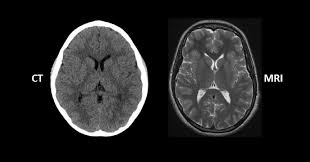

- CT(Computed Tomography): X선을 여러 각도에서 쏜 뒤 컴퓨터로 재구성해 단면 영상을 얻는 검사입니다. 쉽게 말해 고성능 X-ray를 360도에서 찍고 컴퓨터가 합쳐주는 방식입니다.

- MRI(Magnetic Resonance Imaging): 강력한 자기장과 전파를 이용해 인체의 수소 원자 반응을 영상화하는 방식입니다. 방사선을 사용하지 않고 자기장을 이용한다는 점이 CT와 큰 차이입니다.

- CT: 폐, 간, 신장, 뼈처럼 구조가 뚜렷하고 밀도 차이가 큰 장기를 잘 보여줍니다. 특히 교통사고 외상, 뇌출혈, 폐렴, 암 전이 확인 등에 널리 쓰입니다.

- MRI: 뇌, 척수, 근육, 인대, 연골처럼 연부조직(soft tissue)을 정밀하게 볼 수 있습니다. 뇌종양, 허리디스크, 무릎 인대 손상 같은 경우 MRI가 필수적입니다.